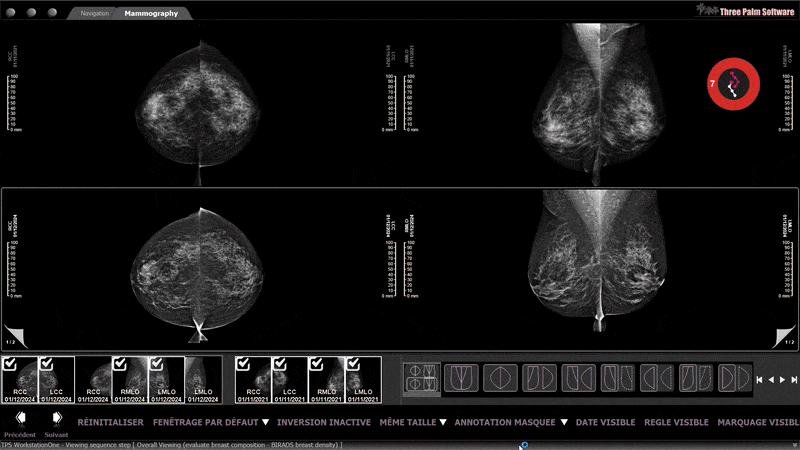

MammoScreen Widget

The MammoScreen Widget is a movable icon that provides a quick, at-a-glance, notification of pertinent information for the case. You will see the MammoScreen Score.

If it is green, you can quickly clear the case. If there is an alert, you can click the widget to see the full MammoScreen report.